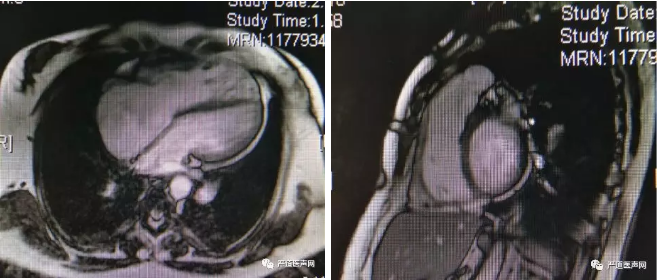

b. CMR检查提示:右心室内径:36mm;左室射血分数(LVEF)=43%;右室射血分数(LVEF)=31%;体表面积校正后左室舒张末容积指数(LVEDVI)= 99.2ml/m2;体表面积校正后右室舒张末容积指数(RVEDVI)= 151ml/m2。

心脏磁共振图像

c. CTA检查提示:肺动脉瓣环内径:31mm;肺动脉内径增宽25mm;肺动脉分叉至瓣环距离41mm。

患者CTA轴位图像